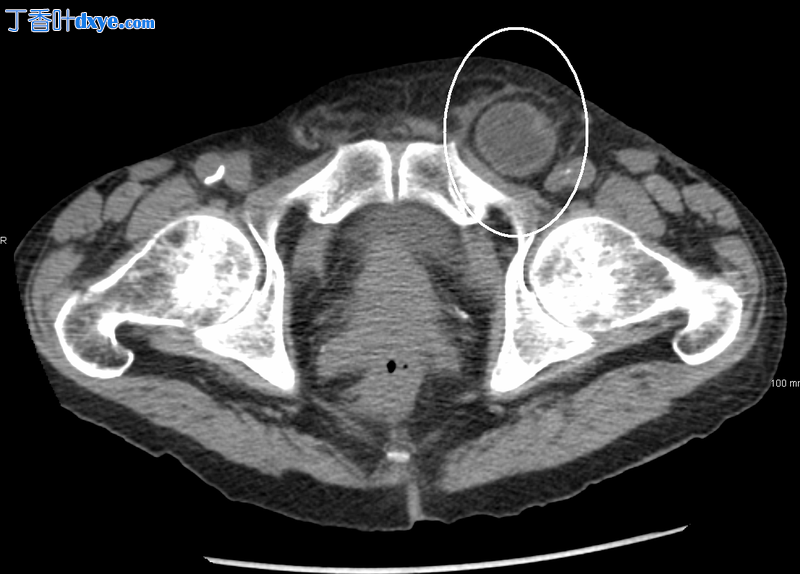

横断面 CT 扫描显示的嵌顿腹股沟疝